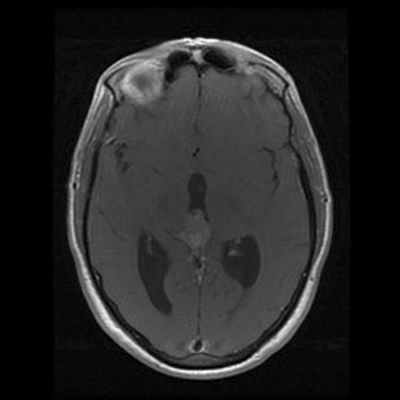

An MRI of the brain with and without contrast revealed a 2.6 x 1.3 x 1.6 cm  (AP x CC X W) heterogenous lesion within the region of the pineal gland and projecting into the third ventricle. The lesion had both solid and cystic components and demonstrated heterogenous enhancement on T1-weighed images. The enhancement is located medial to the veins of Rosenthal, inferior to the cerebral veins, and posterior to the vein of Galen. The mass is isointense to the cortex on T2-weighed images. No significant midline shift or significant edema was observed. The ventricular system was prominent in size, consistent with mild hydrocephalus. Basilar cisterns were preserved and normal cerebrovascular flow-voids were seen.  No abnormalities of the cerebellar or cerebral parenchyma, the brainstem or the cervical spinal cord were observed. Dural venous sinuses and meninges were unremarkable. Regions of the orbit and sella were unremarkable. Paranasal sinuses demonstrated paranasal sinus disease of the bilateral maxillary and left ethmoidal sinuses.

T1+C

T2